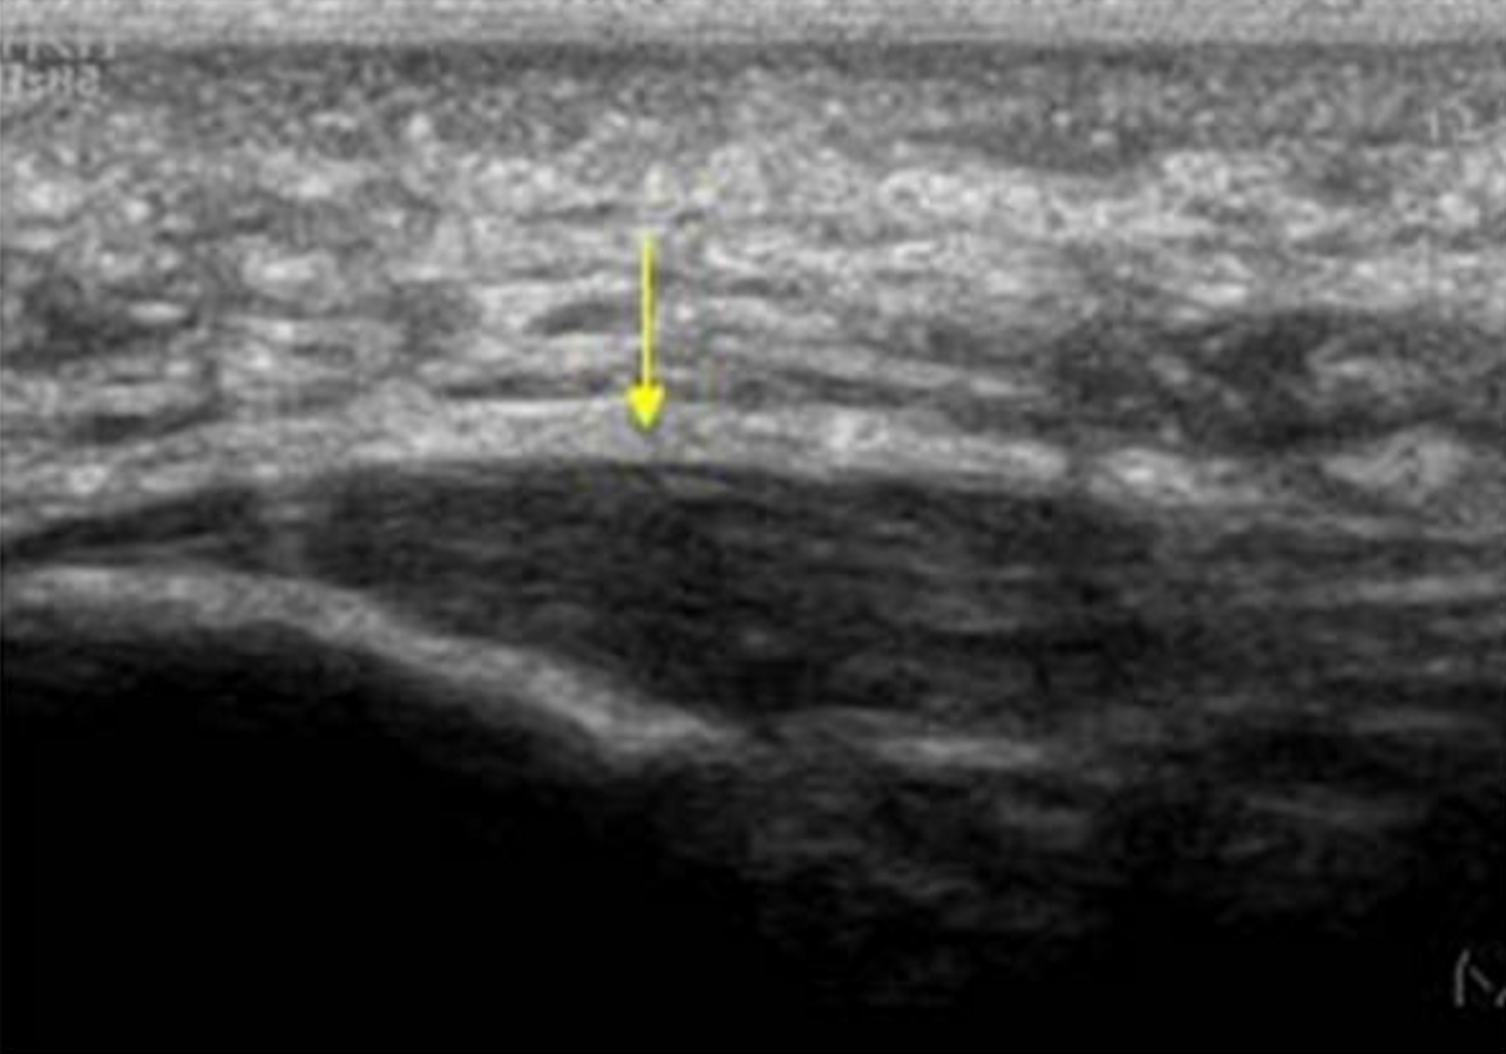

Once confident of your diagnosis, imaging is not generally necessary to begin treatment. If you do have reason to seek imaging, plain radiographs (x-rays- Lateral View) will sometimes show a plantar heel spur, however this is not clinically significant, as the heel spur is very rarely the cause of symptoms. As symptoms of plantar heel pain are due to tissue stress in the plantar soft tissues, the most helpful imaging to confirm diagnosis is a diagnostic MSK ultrasound study. This will usually show thickening of the plantar fasciia. MRI will also show plantar fasciial pathology, and also is useful for ruling out other differential diagnoses, if you are worried about that.

Diagnostic Ultrasound- Useful to confirm thickening of the plantar fascia in plantar fasciitis.